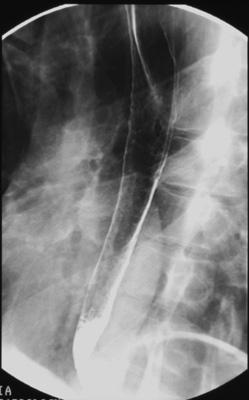

Then, take the empty cup from the

patient and refill it 1/2 full with "bubbly barium". Repeat the same spot images in the

right posterior oblique (RPO) position while the patient holds the cup in

his right hand and drinks an additional 1/2 cup of "bubbly barium". Do not

have the patient stop breathing or swallowing while making the exposures.